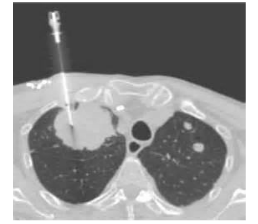

图片10.png

3、CT扫描:CT扫描使用X射线来“拍摄”你身体的详细横断面图像。不像常规的X射线只拍摄一张照片,CT扫描仪在你躺在检查床上围绕你转的时候拍下很多影像。然后计算机会把需要检测病变的身体部位的影像资料转换为一张张的切片照片。比起常规胸部X射线,CT扫描更可能显示肺部肿瘤。同时也能显示任何肺部肿瘤的大小,形状和位置,帮助查找增大了的淋巴结,这些淋巴结可能含有从肺部转移来的肺癌细胞。

图片11.png

图片13.png

如果CT扫描结节或肿块显示有可疑的恶性特性,那么医生将会进行采用以下三种方法对肿瘤进行取样去看看是否有癌细胞(病理诊断),这称为活检。活检包括:

图片14.png图片15.png图片16.png

• 穿刺活检:如果结节在肺的外部,医生可能会把一个细针沿着胸壁的皮肤插进结节中取得活检样本。